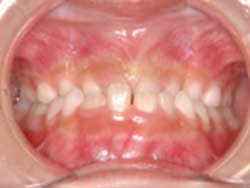

叢生歯列(22歳 女性)

前歯のがたがた、左上犬歯がとび出ていることを主訴として歯科矯正治療を希望された22歳の女性です。小臼歯を抜歯せずに治療するために、歯科矯正用アンカースクリューを用いて歯列を後方に移動してスペースを確保することとしました。